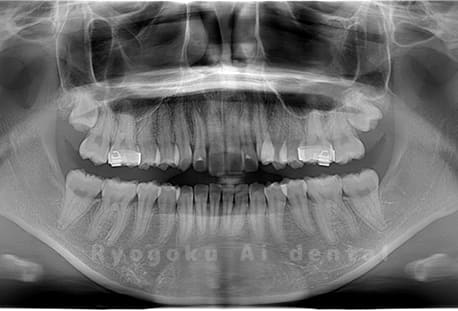

Case02

-

- 原因

- 下顎の水平埋伏智歯

- 治療内容

- 下顎の水平埋伏智歯を抜歯

<リスク・副作用>

手術後は痛み、腫れ、痺れなどの副作用が生じる場合があります。